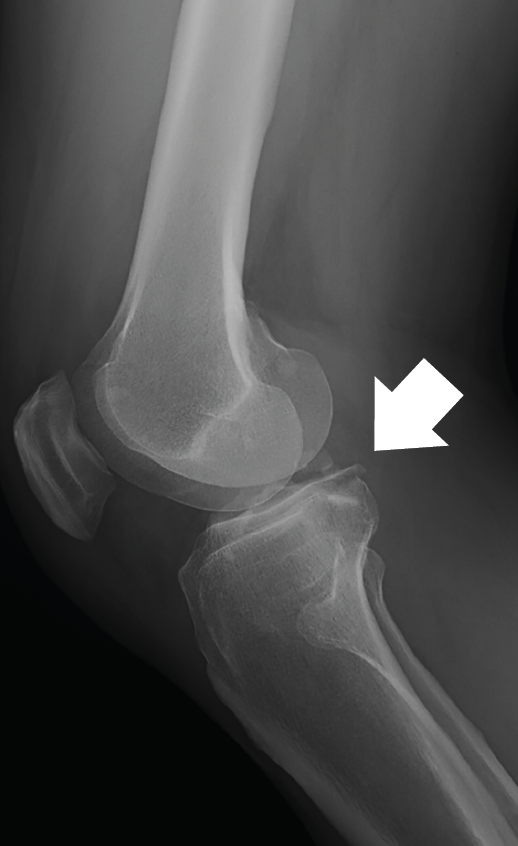

The plain radiographs revealed bone avulsions of the posterior part of the tibia (Figure 1).

Figure 1. Lateral radiographic view of the knee, showing bone involvement in the posterior part of the tibia.